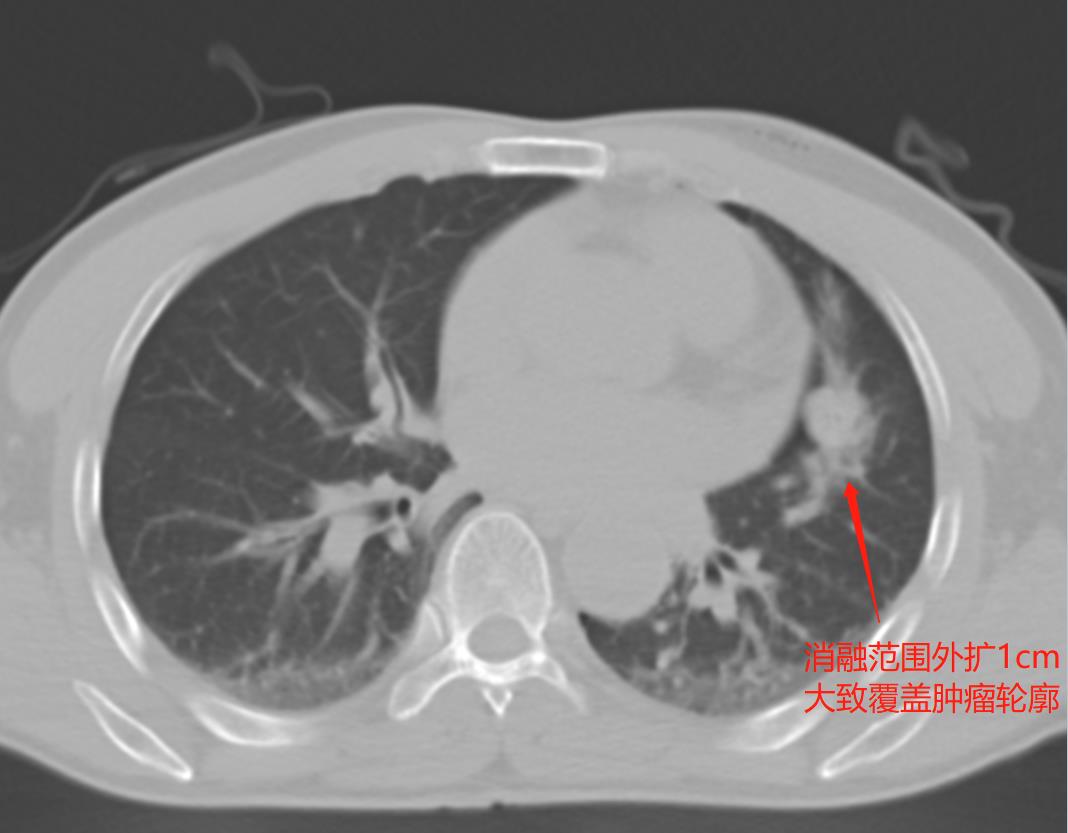

不用切除正常肺组织,也不会影响肺功能,CT介入消融术是真正的“微创”手术,可达成肿瘤的精准爆破,手术是使用一根特制的消融针刺入病变,发射微波,像“微波炉”一样把病变组织“烤熟”,使其失活;为了确保消融效果,一般消融范围需要在病灶外扩至少1cm。

但是在术前的CT评估显示,这个转移瘤紧贴心脏,之间没有任何间隙,给手术团队提了一个难题,如何才能达到安全消融?

做好准备工作,在患者就位后,手术团队轻门熟路的完成了患者的安置、麻醉、术前定位,由CT介入团队的朱柏霖教授主刀,将消融针精准的刺入患者左肺转移瘤的正中位置,使用手术室的滑轨CT扫描确认针尖位置满意、随后朱柏霖教授创新性的通过胸穿针刺入患者左侧胸膜腔人造气胸,利用空气在左肺和心脏之间建立一个间隙,为消融范围外扩留出了安全距离。

在手术团队的多位医生通力合作下,该患者的肺转移瘤消融术毫无悬念成功结束,随后拔针时抽出人造气胸的气体,使肺组织恢复原状,术中即时通过手术室移动式滑轨CT复查显示消融范围覆盖肺转移瘤并安全外扩1cm,患者苏醒顺利,没有任何并发症,手术仅在胸壁上留下了两个一两天内即可愈合的小针眼,术后第二天即可下床活动。